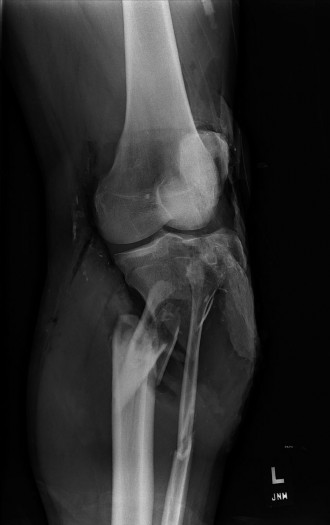

A 20-year-old, male, college football player tackled a fellow teammate in practice and had subsequent pain an…